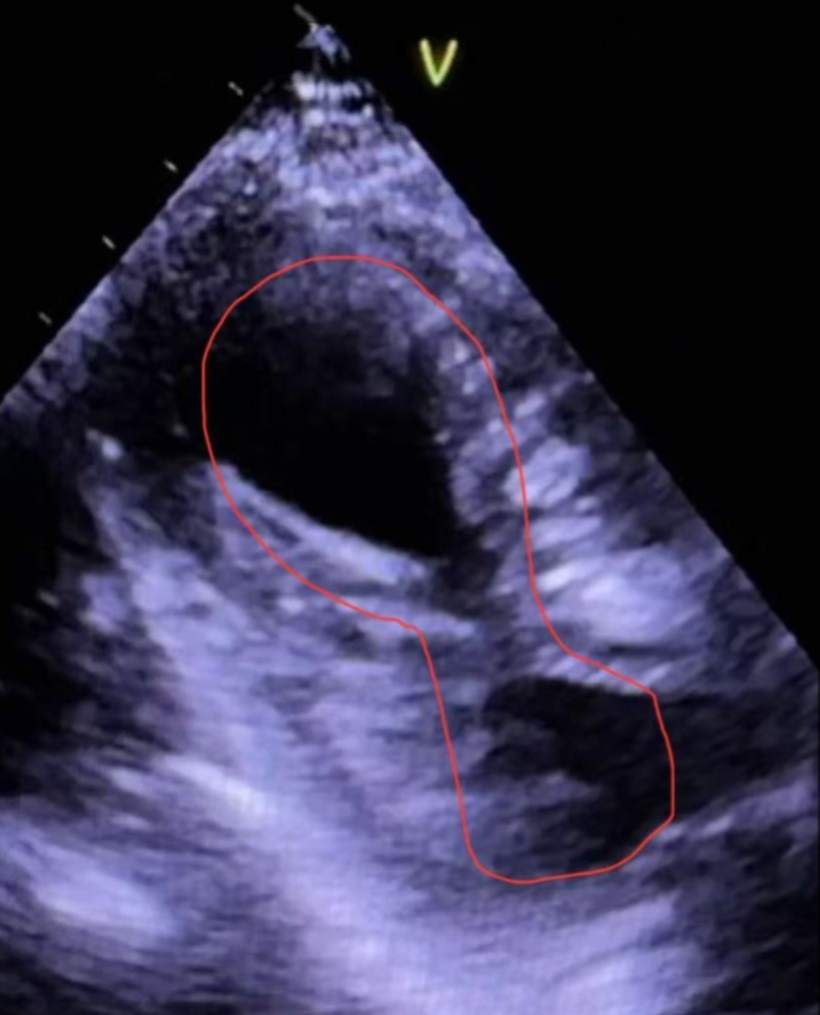

感谢我们医院心超室的叶医生每次都能打出漂亮的心尖球囊样改变的超声动图(即传说中北海道的“章鱼壶”样),让每例应激性心肌病都有一个完美的闭环。

第3例:2025.9.23自己科室的病例。69岁女性。这个病例差点误诊为心肌炎,最后还是靠着心电图这条线索找我们心超室叶医生做了心脏彩超明确。其实这个病人简单一问,病人说咳嗽、胸痛数天就诊,肌钙蛋白升高,当时心电图胸导广泛的无Q波的ST段抬高,冠脉造影阴性,BNP也是轻度升高,有上呼吸道感染症状,理所当然的认为是急性心肌炎了。但后来我一看复查的心电图,又是经典的指向心尖的T波倒置向量,一叫我们心超室叶医生打心脏彩超,又是心尖球囊样改变(即传说中北海道的“章鱼壶”样)。再仔细去问病例,老人家这回说的清清楚楚:那天和老公吵架后生闷气突发胸痛。也是多么经典的情绪应激。看来体现了问病史询问是多么深奥的一门学问……

第4例:2025.9.4自己科室的病例。这个病例更有意思。57岁男性,当时救护车接回说病人是晕厥发病。心电图也是广泛的ST段抬高,肌钙蛋白升高,马上做了冠脉造影是阴性,又是理所当然认为是急性心肌炎。但后来这个病人发现了一个疑点:这个病人说是晕厥,但满身都是挫伤,从上到下,包括下肢、上肢、胸部、头部,还磕掉两颗牙齿。一般晕厥的病人一般不会有这么广泛的挫伤,满身都是,和我们平时见到的晕厥摔伤的病人明显不一样,后来我们叫病人家属把当时在路上发病的监控调出来,病人原来不是晕厥,是脚下绊到了什么东西,严重踉跄狠狠的摔了一跤。心电图的T波倒置不是经典的指向心尖部的向量,虽然心电图不典型,我们还是叫我们心超室叶医生仔细打了心脏彩超,相当漂亮,又是心尖球囊样改变(即传说中北海道的“章鱼壶”样),再次证实是应激性心肌病,当时高温和严重摔伤(创伤)诱发。看来又体现了问病史询问又是多么深奥的一门学问……